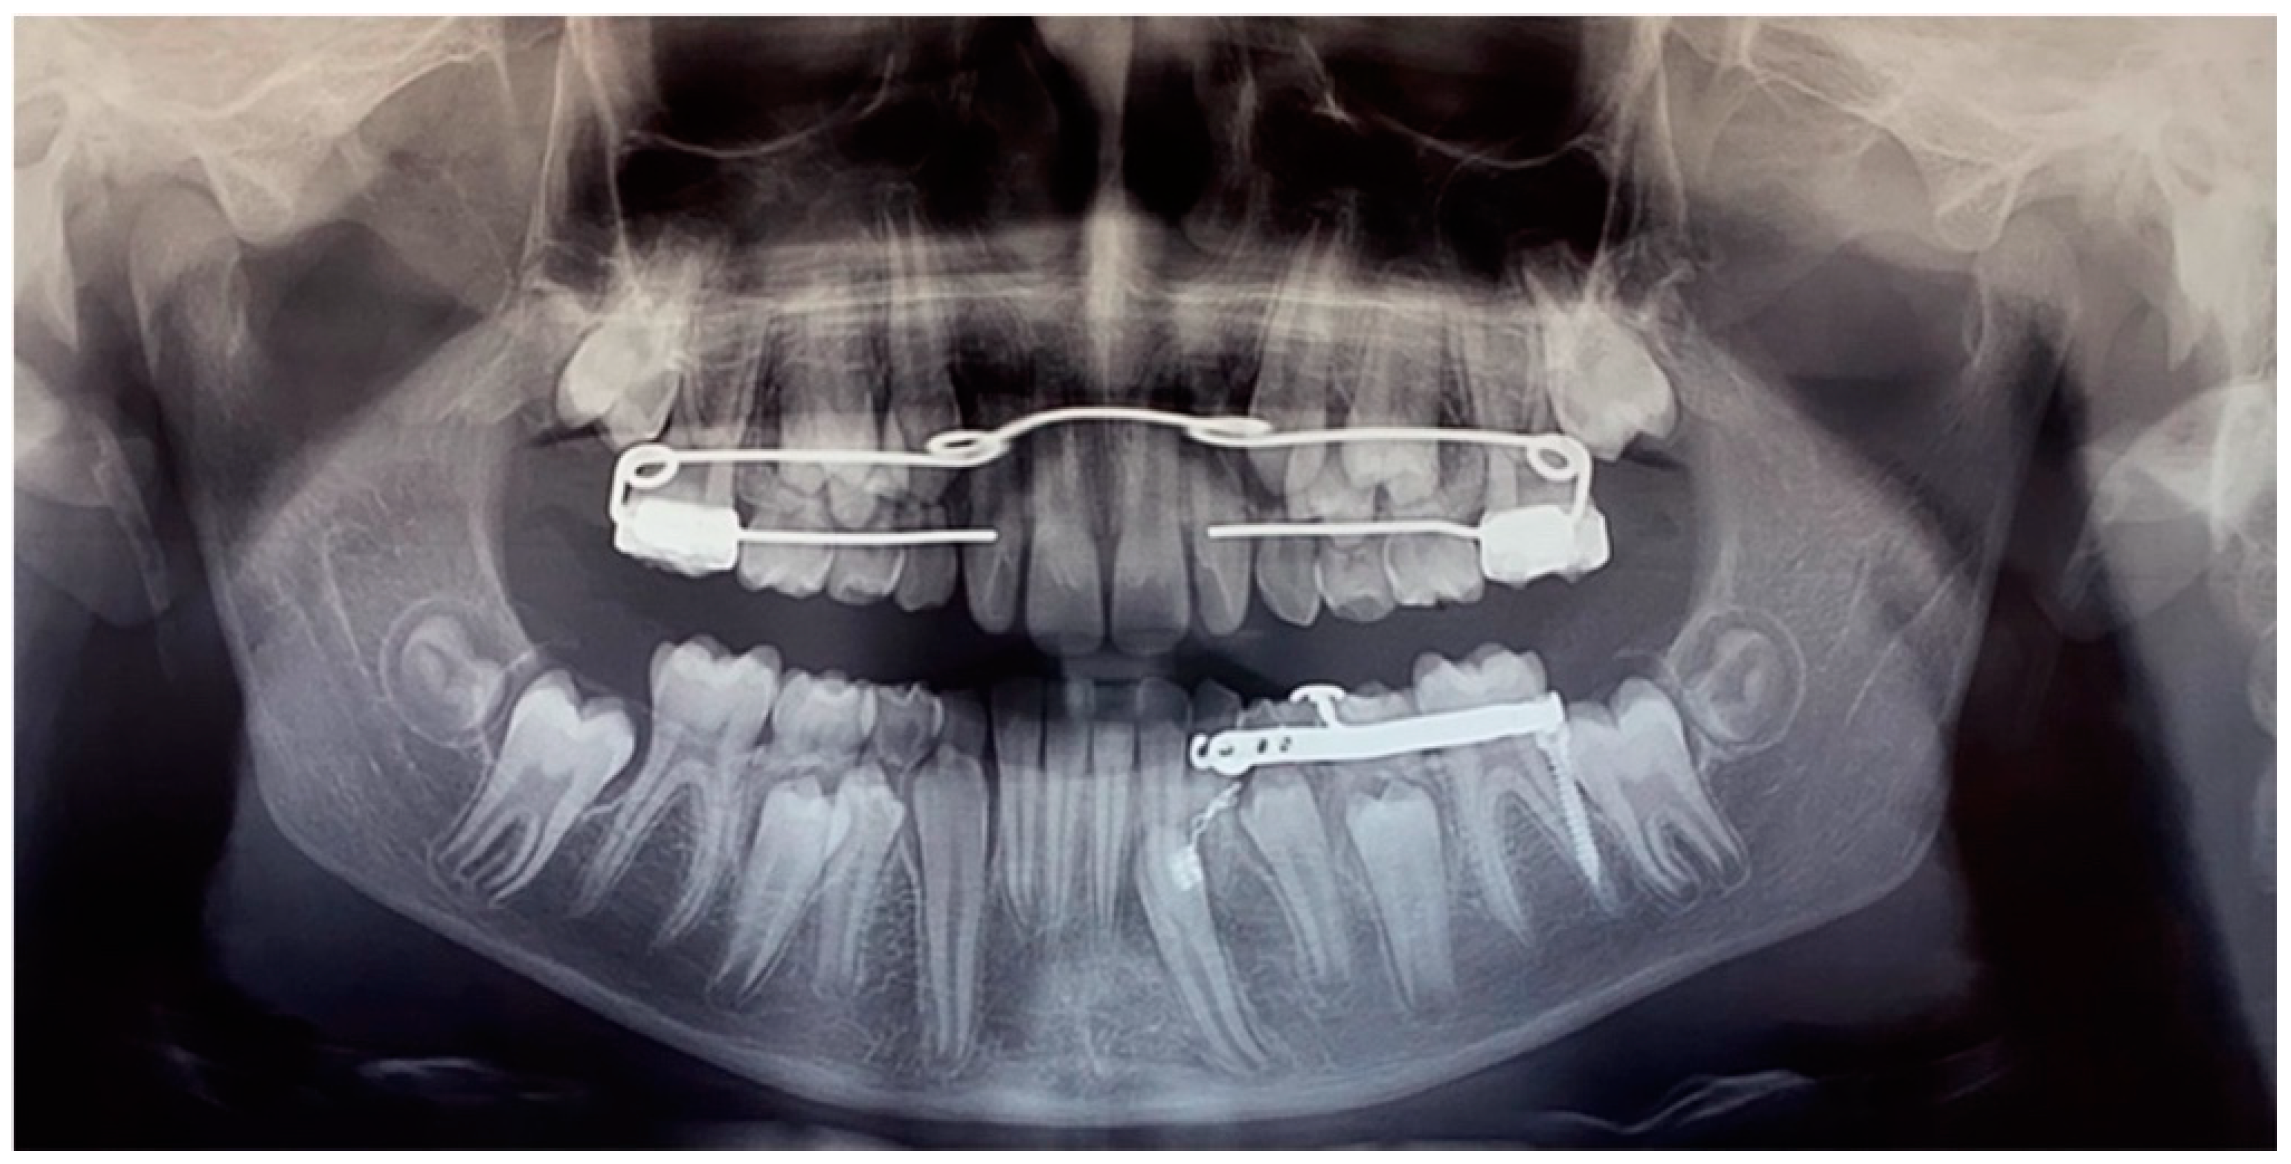

After 12 months, the mandibular canine (element 3.3) was disimpacted, in the axis with its eruptive path and with a correct eruption angle (Figure 13). The crown of the element was visible. The space present and the subject’s still-early mixed dentition was considered favourable to spontaneous eruption and the tooth was allowed to passively erupt. The disimpaction appliance was then removed and the miniscrew, still stable, was removed by unscrewing it.

The tooth element was followed over time through clinical monitoring every month and radiographic follow-up every 6 months (Figure 14).

Figure 13. Panoramic radiograph at the end of the orthodontic traction with the customized skeletal anchorage device.